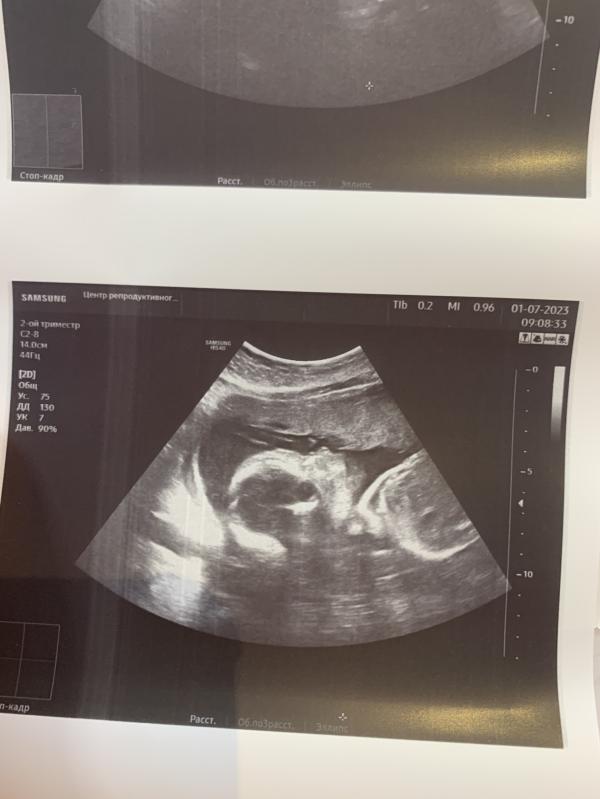

Наконец то наш мальчик показался в профиль 🙌

23,4 недели .

Вес 540 гр